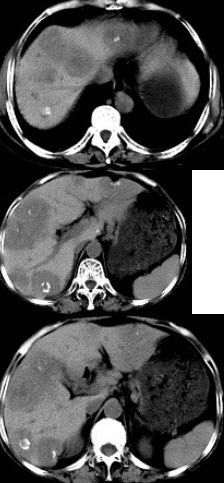

女性,50岁,曾患乙型肝炎,肝硬化多年,右上腹胀痛1月余,CT检查如图所示,最全面的诊断是( )

A:肝硬化、腹水伴胆管细胞癌

B:肝硬化、腹水伴原发性肝癌

C:肝硬化、腹水、肝癌并门脉癌栓

D:肝硬化、腹水并肝脓肿

E:肝硬化、腹水并肝血管瘤